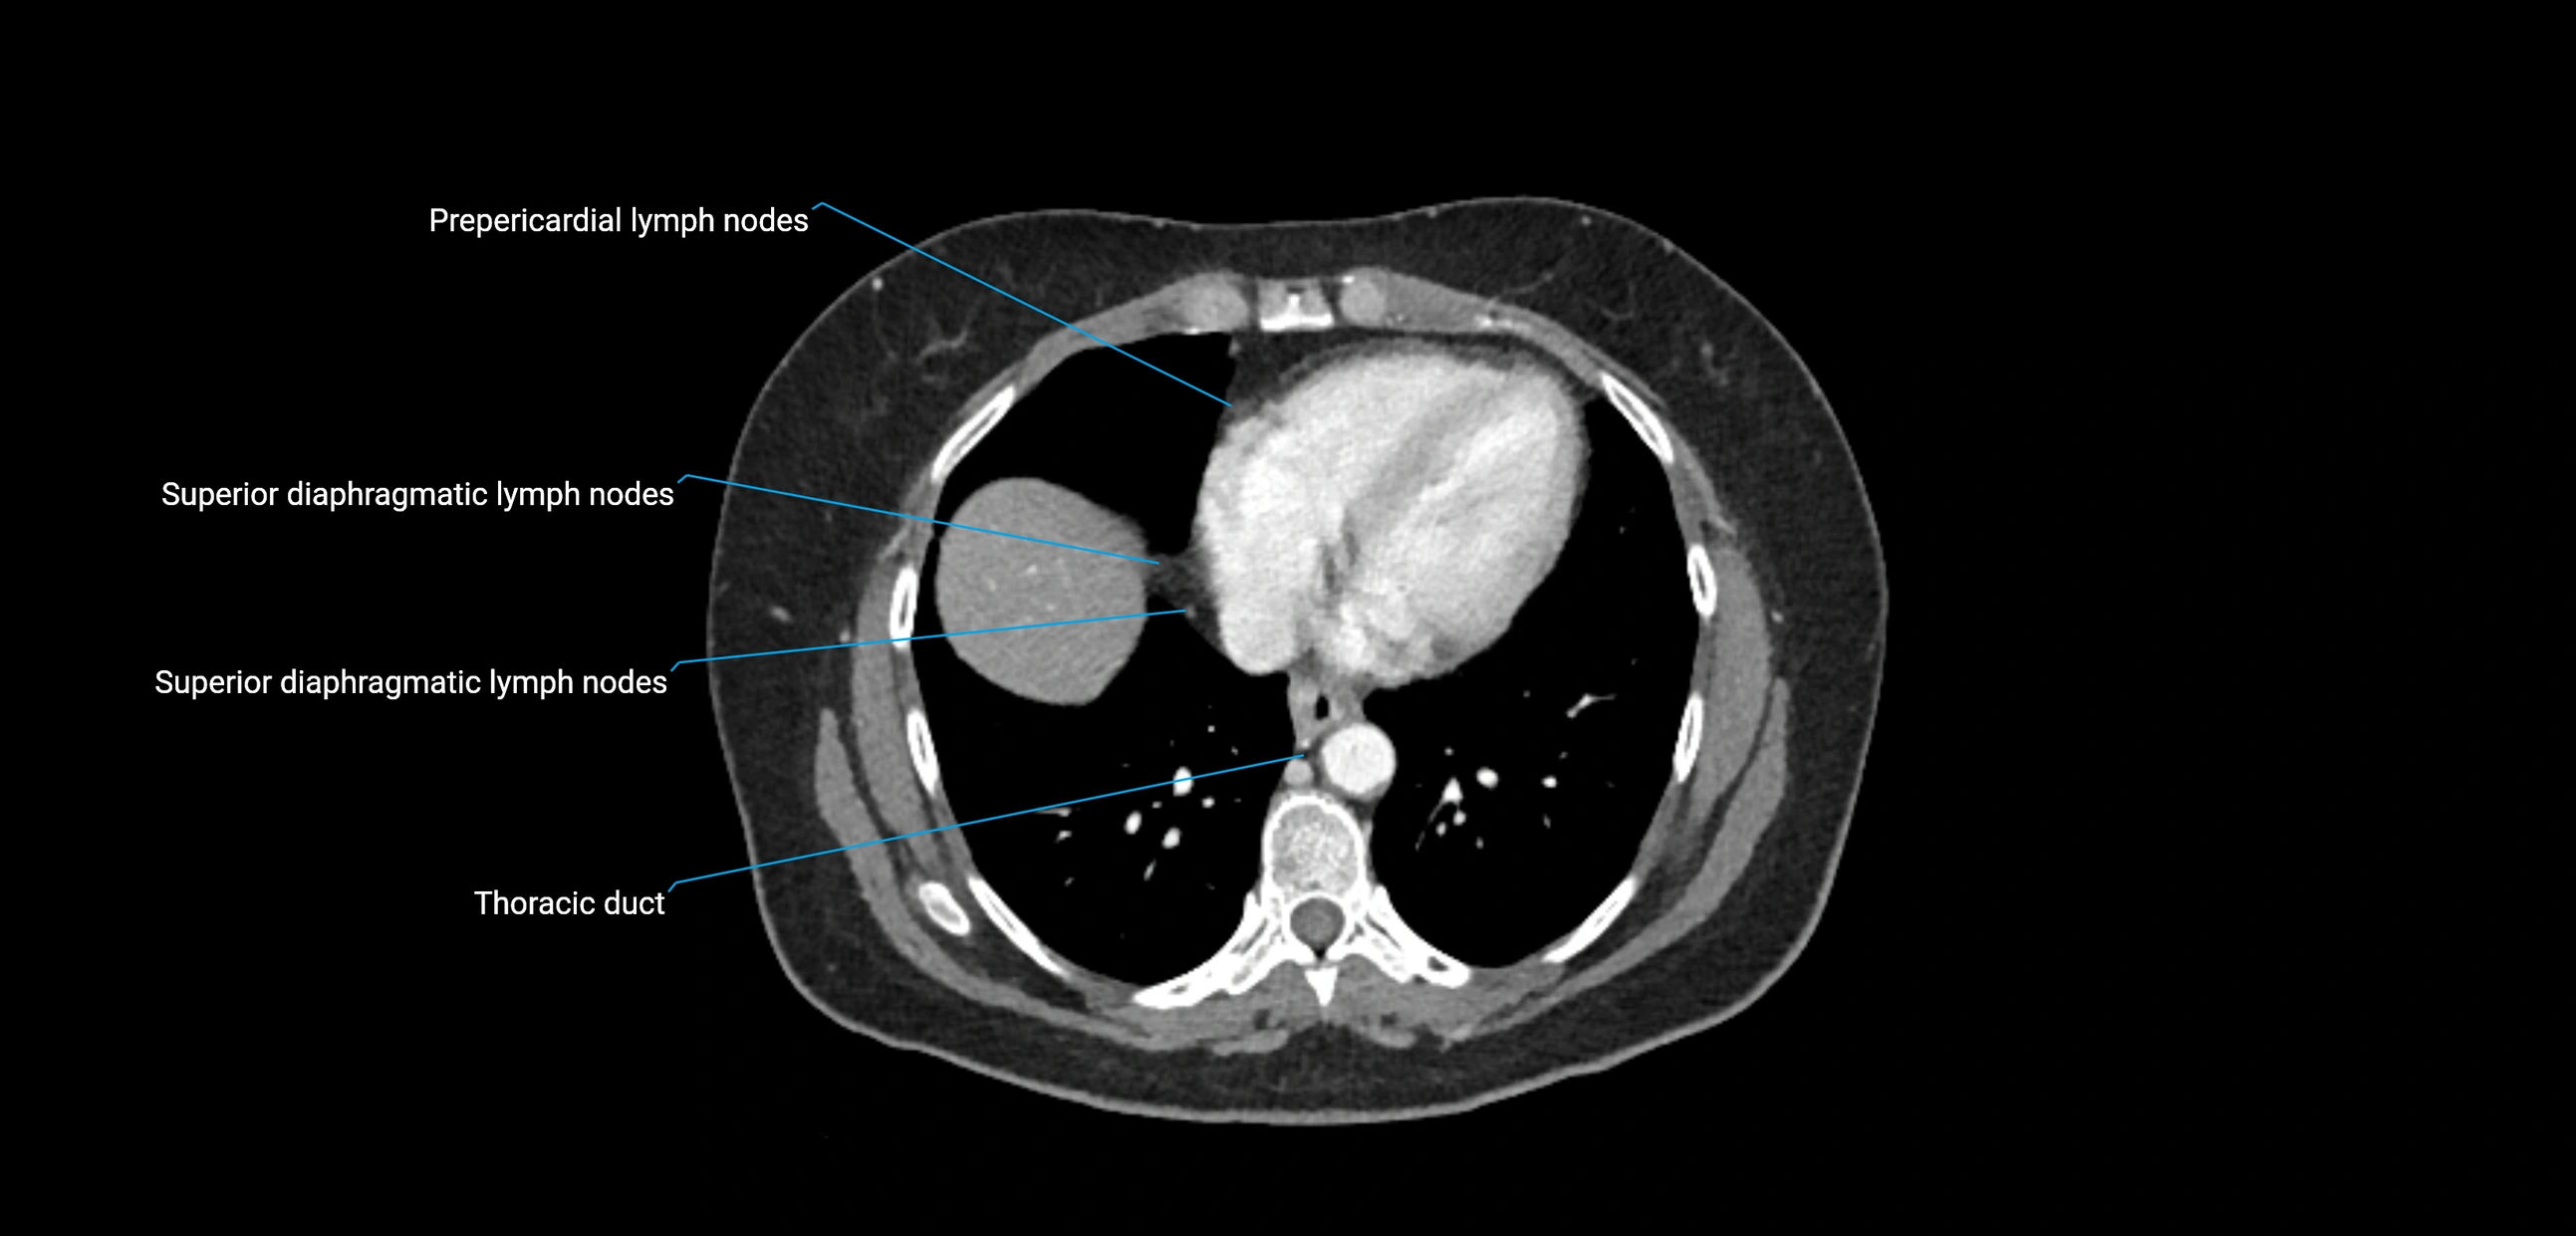

CT image

image